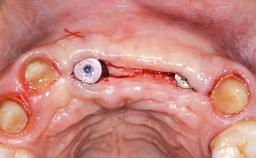

Replacement of Two Central Incisors with Non-Splinted Crowns on Bone-Level Implants

A 27-year-old female patient was referred to the Clinic of Oral Surgery and Stomatology of the University of Bern due to acute pain in the region of her two maxillary central incisors. The patient was in good general health. She reported a bicycle accident approximately 5 years earlier in which teeth 11 and 21 had been traumatized but neither fractured nor displaced. Several weeks after the accident, endodontic treatment was performed on both central incisors, although the patient did not recall the precise reasons for this decision. About 2 years ago, non-vital bleaching had been conducted, in accordance with the “walking-bleach” principle, due to progressive discoloration of teeth 11 and 21.